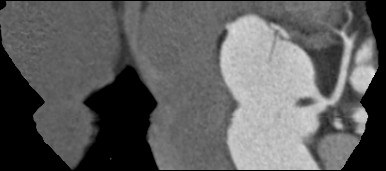

标题: CT24400:患者54岁,心前区不适进行心脏冠脉造影检查。 [打印本页]

标题: CT24400:患者54岁,心前区不适进行心脏冠脉造影检查。

患者54岁,心前区不适进行心脏冠脉造影检查。高手看看有问题没有?

图像很漂亮,好像未见异常